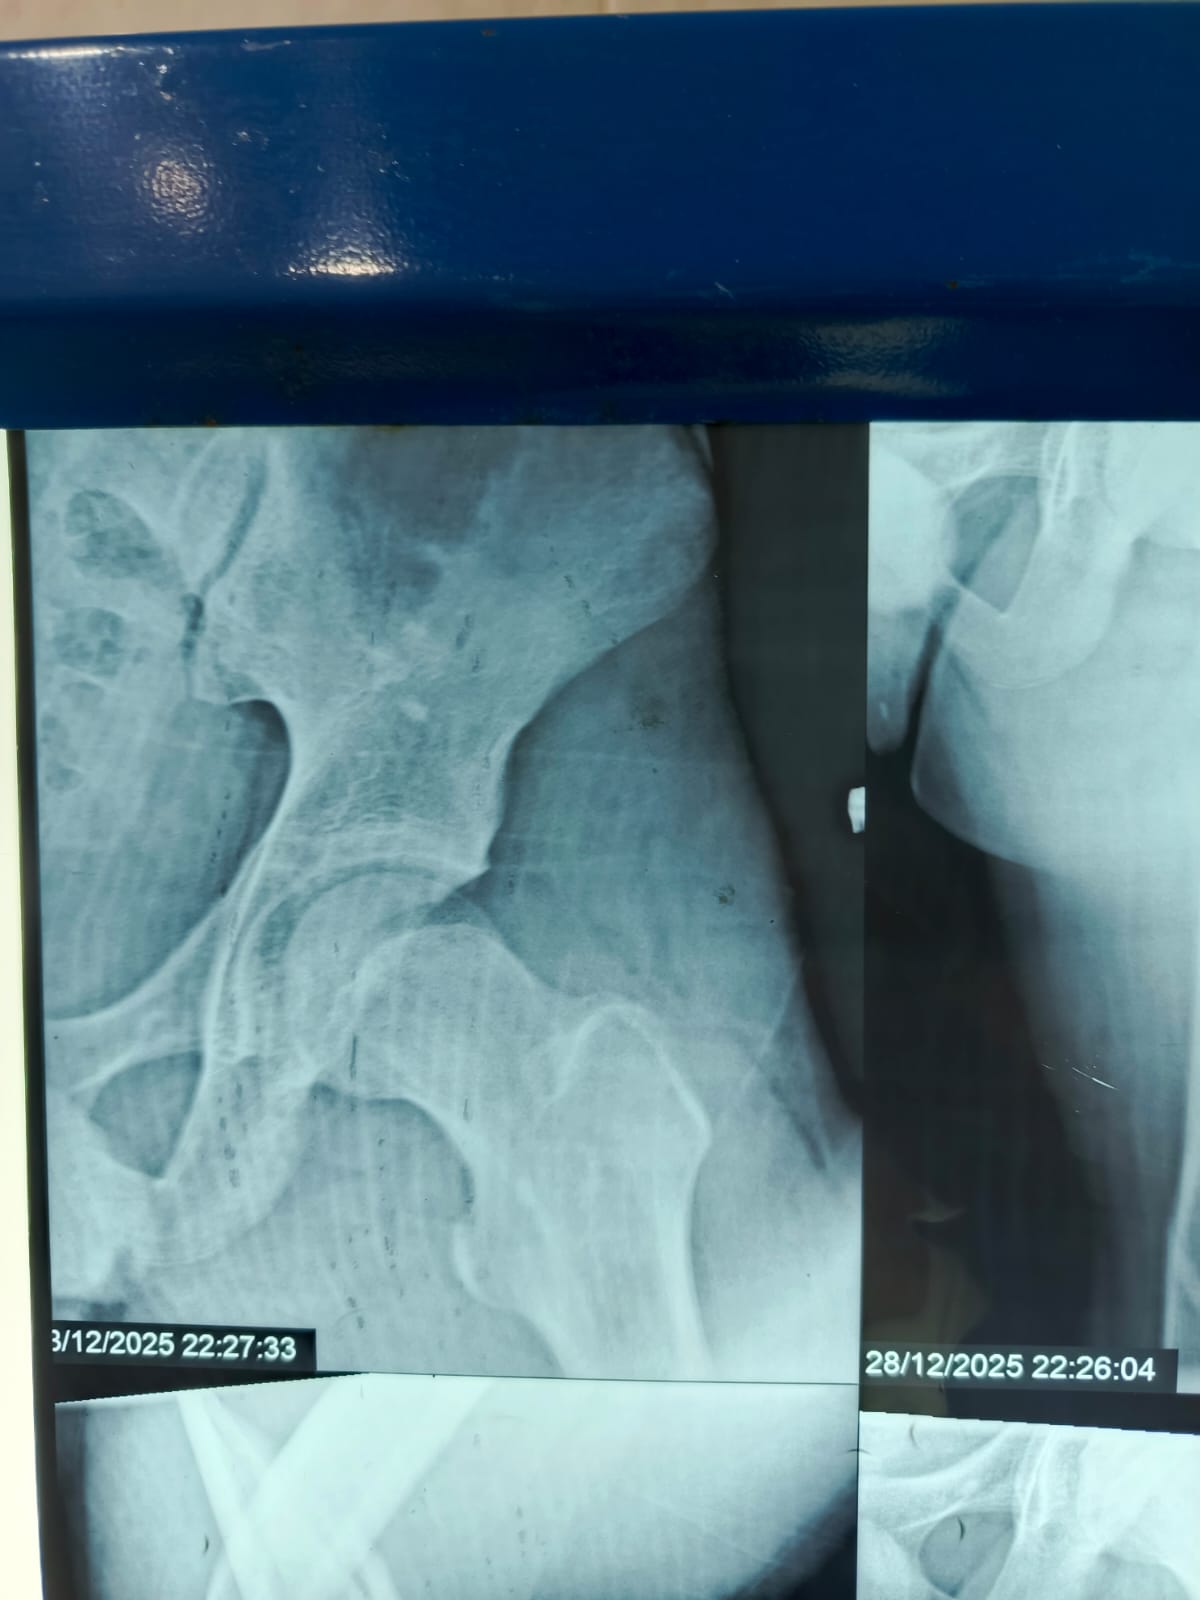

مستشفى مغاغة العام ينقذ شاباً مصاباً بكسر معقد في الفخذ بعد حادث مروري

حقق الفريق الطبي بمستشفى مغاغة العام بمحافظة المنيا إنجازاً طبياً جديداً، بعدما نجح في إنقاذ شاب يبلغ من العمر 16 عاماً، وصل إلى المستشفى إثر حادث مروري عنيف أسفر عن كسر مفتت متعدد المواضع بعظمة الفخذ الأيسر، في تدخل عكس سرعة الاستجابة وكفاءة التعامل مع الحالات الطارئة.

تدخل جراحي سريع بتقنيات حديثة

استنفرت أطقم الطوارئ جهودها فور وصول المصاب، واتخذ الفريق الطبي قراراً عاجلاً بإجراء جراحة المسمار النخاعي التشابكي دون فتح موضع الكسر، ما ساهم في تقليل المضاعفات وتسريع وتيرة العلاج.

أنهى الفريق الجراحي العملية خلال ساعتين ونصف، وخرج الشاب من غرفة العمليات في حالة مستقرة، وفق معايير طبية حديثة تعتمد على التدخل محدود الجروح، وتقليل فقدان الدم، وخفض فرص العدوى، مع تسريع معدلات التئام العظام مقارنة بالأساليب التقليدية.